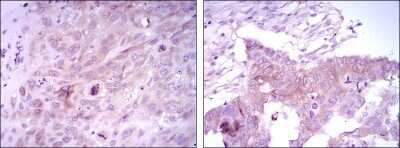

Immunohistochemistry-Paraffin: FoxD3 Antibody (5G9) - BSA Free [NBP1-51685]

Immunohistochemistry-Paraffin: FoxD3 Antibody (5G9) [NBP1-51685] - Analysis of paraffin-embedded lung cancer tissues (left) and ovarian cancer tissues (right) using FOXD3 mouse mAb with DAB staining.